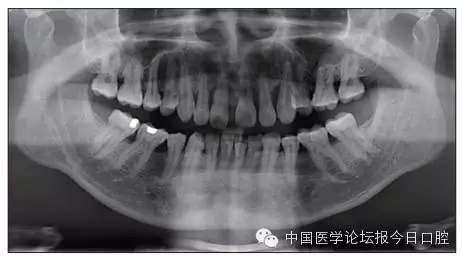

全口曲面體層片(圖3)顯示,患者全牙列牙槽骨吸收;根尖片(圖4)示11近中牙槽骨角形吸收已達根尖1/3,21牙槽骨嵴頂吸收至根1/2,23牙槽骨近中骨板角形吸收至根1/2。磨牙區(qū)骨嵴頂吸收3mm。治療前頭顱側位片見圖3,治療前ODS模型見圖5。

圖3 治療前頭顱側位片及曲面體層片